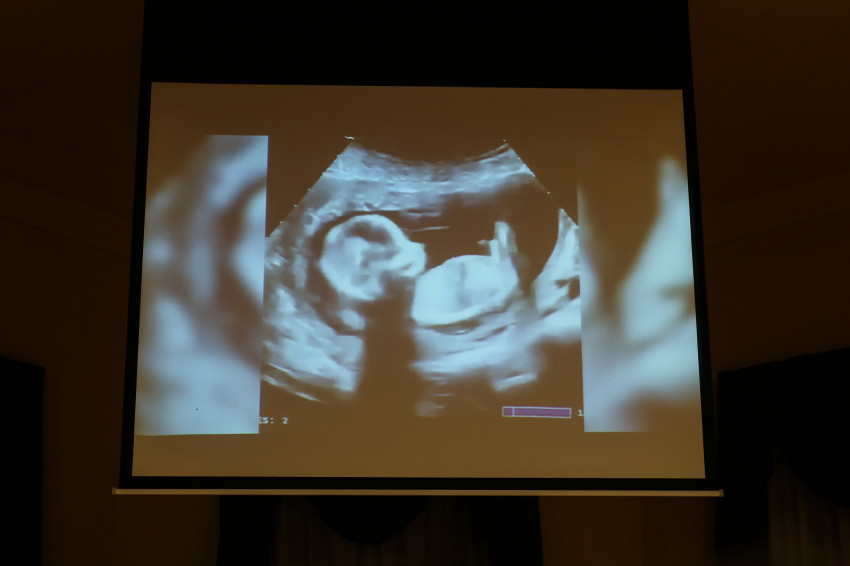

Az elmúlt két évben az USA kilenc államának – Iowa mellett Alabama, Dél-Dakota, Georgia, Kentucky, Louisiana, Mississippi, Missouri, Ohio – kormányzója írta alá azt a jogszabályt, amely valamilyen formában tartalmazza a szívdobbanás-koncepciót. Eszerint az ultrahangvizsgálat kimutatja az anyának gyermeke szívdobbanását, a törvény pedig védi a magzat életét szíve első dobbanásától – körülbelül a várandósság hatodik hetétől.

A doktornő rendkívüli jelentőségűnek nevezte a szívdobbanás-koncepciót, mert rávilágít: a megfogant és fejlődő magzat emberi élet, nem pedig sejtcsomó.